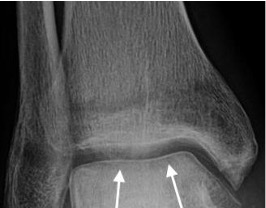

- The ‘Hawkin's sign' describes subchondral lucency of the talar dome 6-8 weeks after a talar neck fracture; indicates sufficient vascularity in the talus

- Absence of the Hawkins sign, seen as subchondral sclerosis may indicate disruption to the blood supply of the talar dome and underlying AVN

Hawkin’s sign with subchondral lucency of the talar dome (arrows)